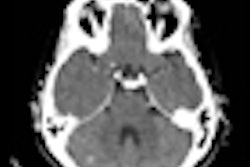

| MDCT-derived structure measures of osteoporotic spines showed only limited correlations to the trabecular bone structure (BV/TV) and trabecular thickness (Tb.Th.). However, MDCT density measures were well correlated to trabecular bone density (vBMD). |

"MDCT highly overestimates trabecular thickness, but what's more interesting is the correlation between μCT and MDCT," Issever said. "What we find again is that [bone-mineral] density-based measures such as vBMD or BV/TV show higher correlations with μCT. Trabecular thickness shows moderate correlations ... we believe due to partial-volume effect."